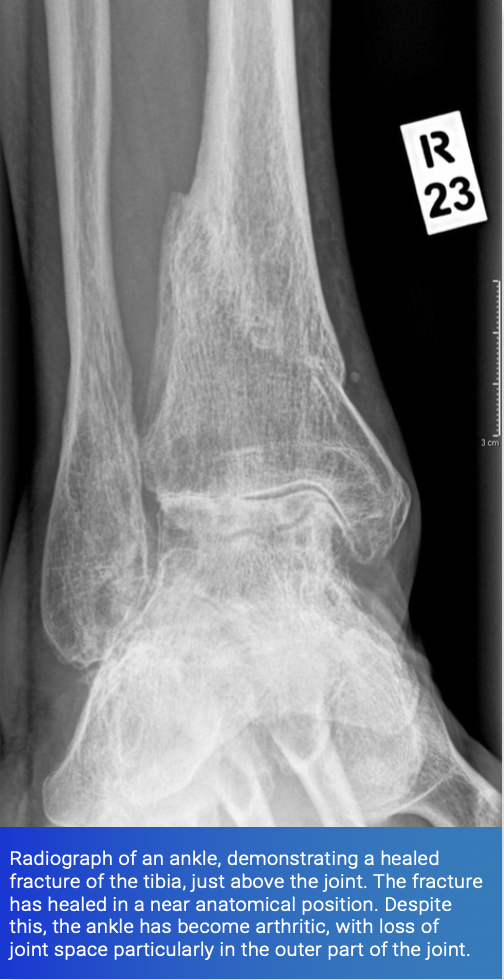

Intra-articular fractures occur when a large amount of force passes through a joint. Such a fracture may breach the bone and cartilage of the joint. This results in irregularities or even steps in the hyaline cartilage. These fractures can either be undisplaced and amenable to non-operative treatment or displaced, in which case surgery may be considered.

The risk of post-traumatic arthritis is particularly increased when the joint surface heals in a non-anatomical position. This can alter the biomechanics of the joint. Irregularities and steps in the cartilage predispose to arthritic change, although the height of step that is significant is difficult to estimate, and varies joint by joint. Evidence around this subject is contentious. A good rule of thumb is that if the step is greater than the thickness of cartilage in the joint, the outcome is likely to be unfavorable.

When assessing the risks of a patient developing post-traumatic arthritis after an intra-articular fracture, particular attention is paid to the degree of comminution at the fracture site. This is the number of fracture fragments that are present - the greater the number, the higher the force applied and the greater the potential damage to the joint surface, resulting in an increased risk of the development of arthritis.